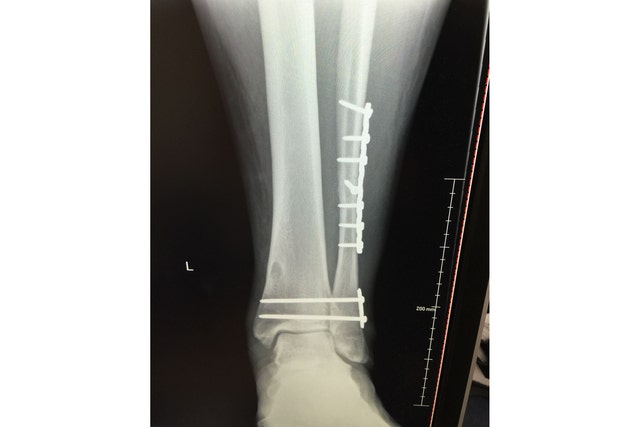

• The Cowboys didnt win Thursday nights epic passing battle between Dak Prescott and Tom Brady. Playing his first game since suffering a gruesome ankle injury 11 months ago and then signing a 160 million contract Dak Prescott was outstanding against a defense that shut down Patrick Mahomes in the Super Bowl and returned every starter. Emotional Dallas Cowboys quarterback Dak Prescott suffers GRUESOME ankle injury as hes carted off the field in tears against New York Giants. Updated 343 AM ET Wed October 14 2020. Silverman is no stranger to breaking down the forces of nature that result in an athletes injury as well as their expected recovery protocol. Orthopedic Surgeon Explains Dak Prescotts Ankle Fracture.

Dak Prescotts gruesome ankle injury will only take Dallas season from bad to worse. The bottom line is hes there. Prescott was in tears as he was carted off of the field raising a fist to the Cowboys crowd before being taken to the back for what will surely be X-rays and an MRI to determine the exact extent. Dak Prescott suffered a horrific season-ending injuring Sunday –snapping his ankle in the worst possible way requiring emergency surgery. The Dallas Cowboys QB was.

Silverman is no stranger to breaking down the forces of nature that result in an athletes injury as well as their expected recovery protocol. AP Dak is back and hes still not enough for the Dallas Cowboys. Orthopedic Surgeon Explains Dak Prescotts Ankle Fracture. The bottom line is hes there. Dak Prescott suffered a horrific season-ending injuring Sunday –snapping his ankle in the worst possible way requiring emergency surgery.